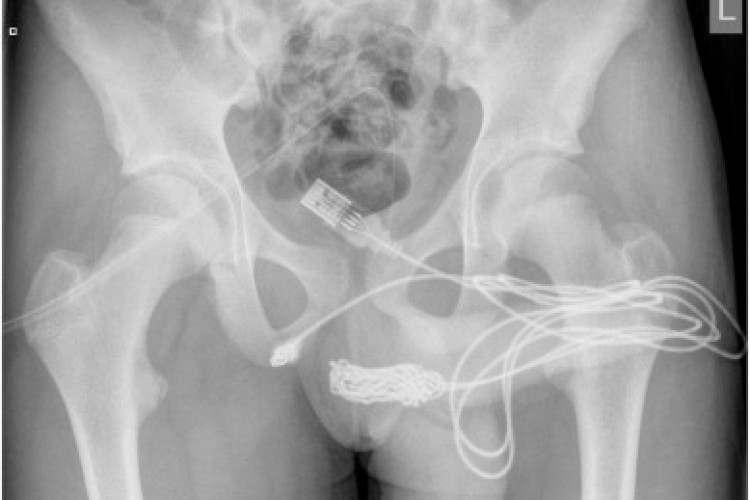

O adolescente teria tentado tirar o cabo à força antes de ir ao hospital, mas não conseguiu por causa dos nós do fio. De acordo com a publicação, as pontas do cabo USB estava projetadas do lado externo do órgão, enquanto o meio do cabo, com vários nós, estava dentro da uretra. Após tentativas de retirada no hospital local, ele foi transferido com urgência ao University College Hospital em Westmoreland Street, em Londres.

Lá, o menino foi submetido a uma uretrostomia penoescrotal, procedimento no qual os médicos fazem um corte entre a genitália e o ânus do paciente.